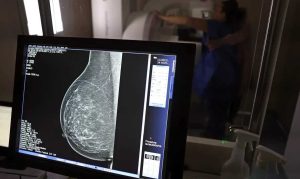

Falta de acesso a mamógrafos limita prevenção do câncer de mama

No mês de conscientização sobre o câncer de mama, um relatório destaca a importância de acesso igualitário ao rastreamento e tratamento da doença. Segundo o Atlas da Radiologia no Brasil, do Colégio Brasileiro de Radiologia e Diagnóstico por Imagem (CBR), o acesso aos mamógrafos ainda é um desafio.

O país tem 6.826 equipamentos registrados, sendo 96% em funcionamento. Metade deles está disponível no Sistema Único de Saúde (SUS), responsável por atender 75% da população. Isso equivale a 2,13 mamógrafos por 100 mil habitantes dependentes do SUS.

O Brasil tem uma cobertura muito baixa de mamografias: 24%. O ideal recomendado pela Organização Mundial da Saúde é de 70%. Mesmo em lugares como o estado de São Paulo, que tem a maior concentração de mamógrafos do país, a taxa gira em torno de 26%.

“O que é efetivo na redução da mortalidade é você descobrir o tumor antes de ter sintoma clínico. Quanto menor o tumor, melhor para a gente descobrir o tratamento e maior a chance de cura. E a gente só consegue fazer isso com exames de imagem”, diz Ivie.

Ela explica que no caso de diagnóstico de um câncer de mama com menos de 1 cm, a chance de cura é de 95% em cinco anos, independentemente se ele é do tipo mais agressivo. “E esses tumores só vão ser detectados na mamografia. Essas pessoas que têm que ir fazer mamografia são mulheres saudáveis. Não são mulheres doentes”, acrescenta.